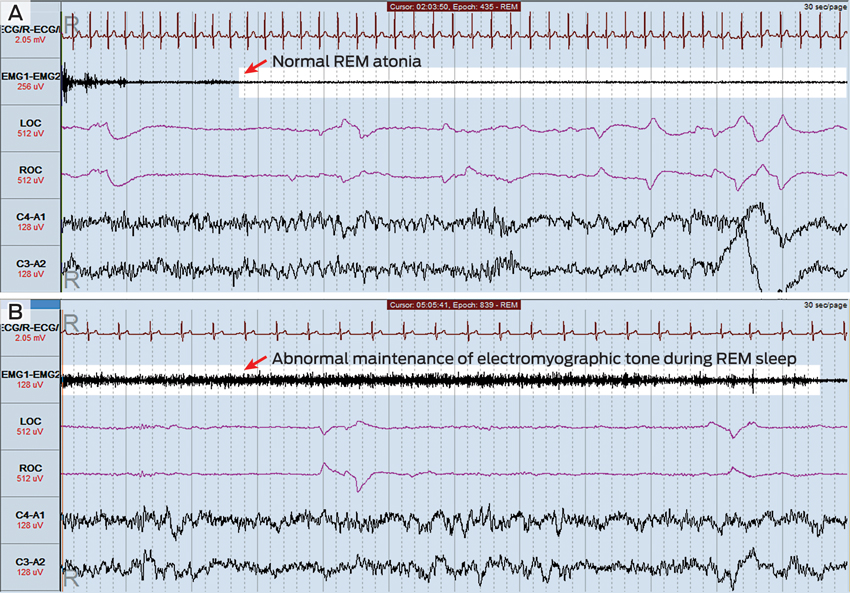

The patient underwent overnight laboratory-based polysomnography (Figure) with video monitoring. Total sleep time was 404 minutes, with a normal sleep efficiency (time asleep ÷ time in bed) of 85.7%, a normal arousal index of 9.3 events/hour and a normal apnoea–hypopnoea index of 0.7 events/hour. Minor periodic limb movements were detected but were not associated with electroencephalographic arousals.

During periods of rapid eye movement (REM) sleep, abnormal motor activity was detected (Figure, B). Muscle tone, as measured by electromyographic tone, actually increased during some periods of REM sleep, and phasic limb movements were seen during these periods. The patient thrashed his arms around on a number of occasions during REM sleep, but no other violent motor activity was detected. There was no evidence of seizure activity on the electroencephalogram recording. The polysomnography findings were thought to be consistent with a diagnosis of REM sleep behaviour disorder.

RBD can be idiopathic or associated with an underlying neuropathological condition, particularly the α-synucleinopathies Parkinson disease, Lewy body dementia and multisystem atrophy.4 Up to 65% of patients with RBD develop one of these conditions after a variable lag period, which is sometimes measured in decades.5 In addition, RBD is diagnosed in significant numbers of patients with a known α-synucleinopathy.6 Arousals during REM sleep due to obstructive sleep apnoea can mimic features of RBD, making this an important differential diagnosis.7 Diagnosis of RBD requires suggestive clinical features and abnormalities detected on overnight polysomnography, particularly the maintenance of electromyographic tone during the REM stage of sleep and associated phasic limb movements.